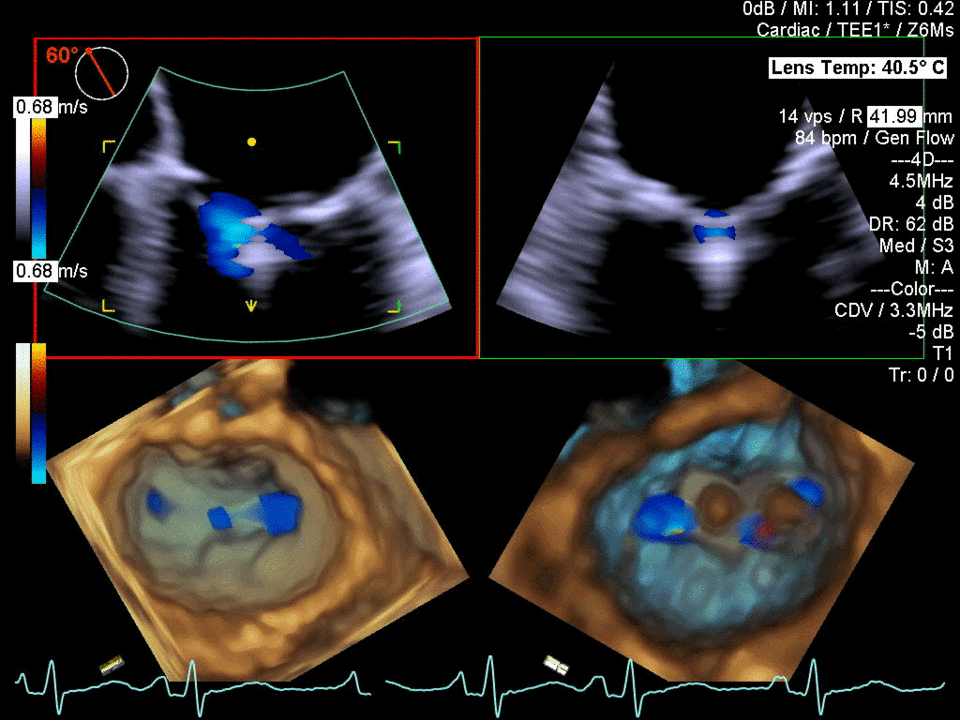

İKİNCİ DÜZEY (İLERİ DÜZEY) ULTRASONOGRAFİ

Ayrıntılı ultrasonografi veya detaylı ultrasonografi veya ileri düzey (ikinci düzey) ultrasonografi aynı anlamdadır.